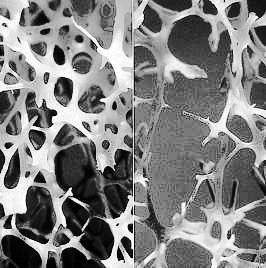

Alimentul care previne depunerea colesterolului pe vasele de sânge și combate osteoporoza